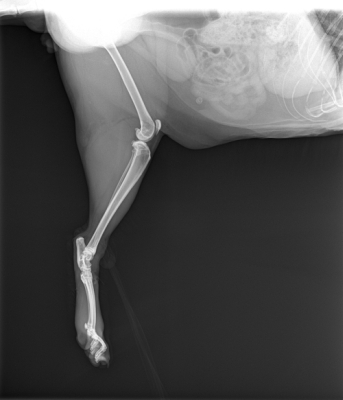

私は腰周りの骨折も心配だったので、先生に頼んで全身のレントゲンをお願いしました。

そして、レントゲンの結果、チャトラの脚は骨折していなかったことが分かったのです。

先生の見立てでも骨折っぽい歩き方だったそうですが、幸いにも脚や腰周りに骨折した部分はありませんでした。

ただ、ケガはかなり深い様子だったため、1針縫合して治療することになりました。